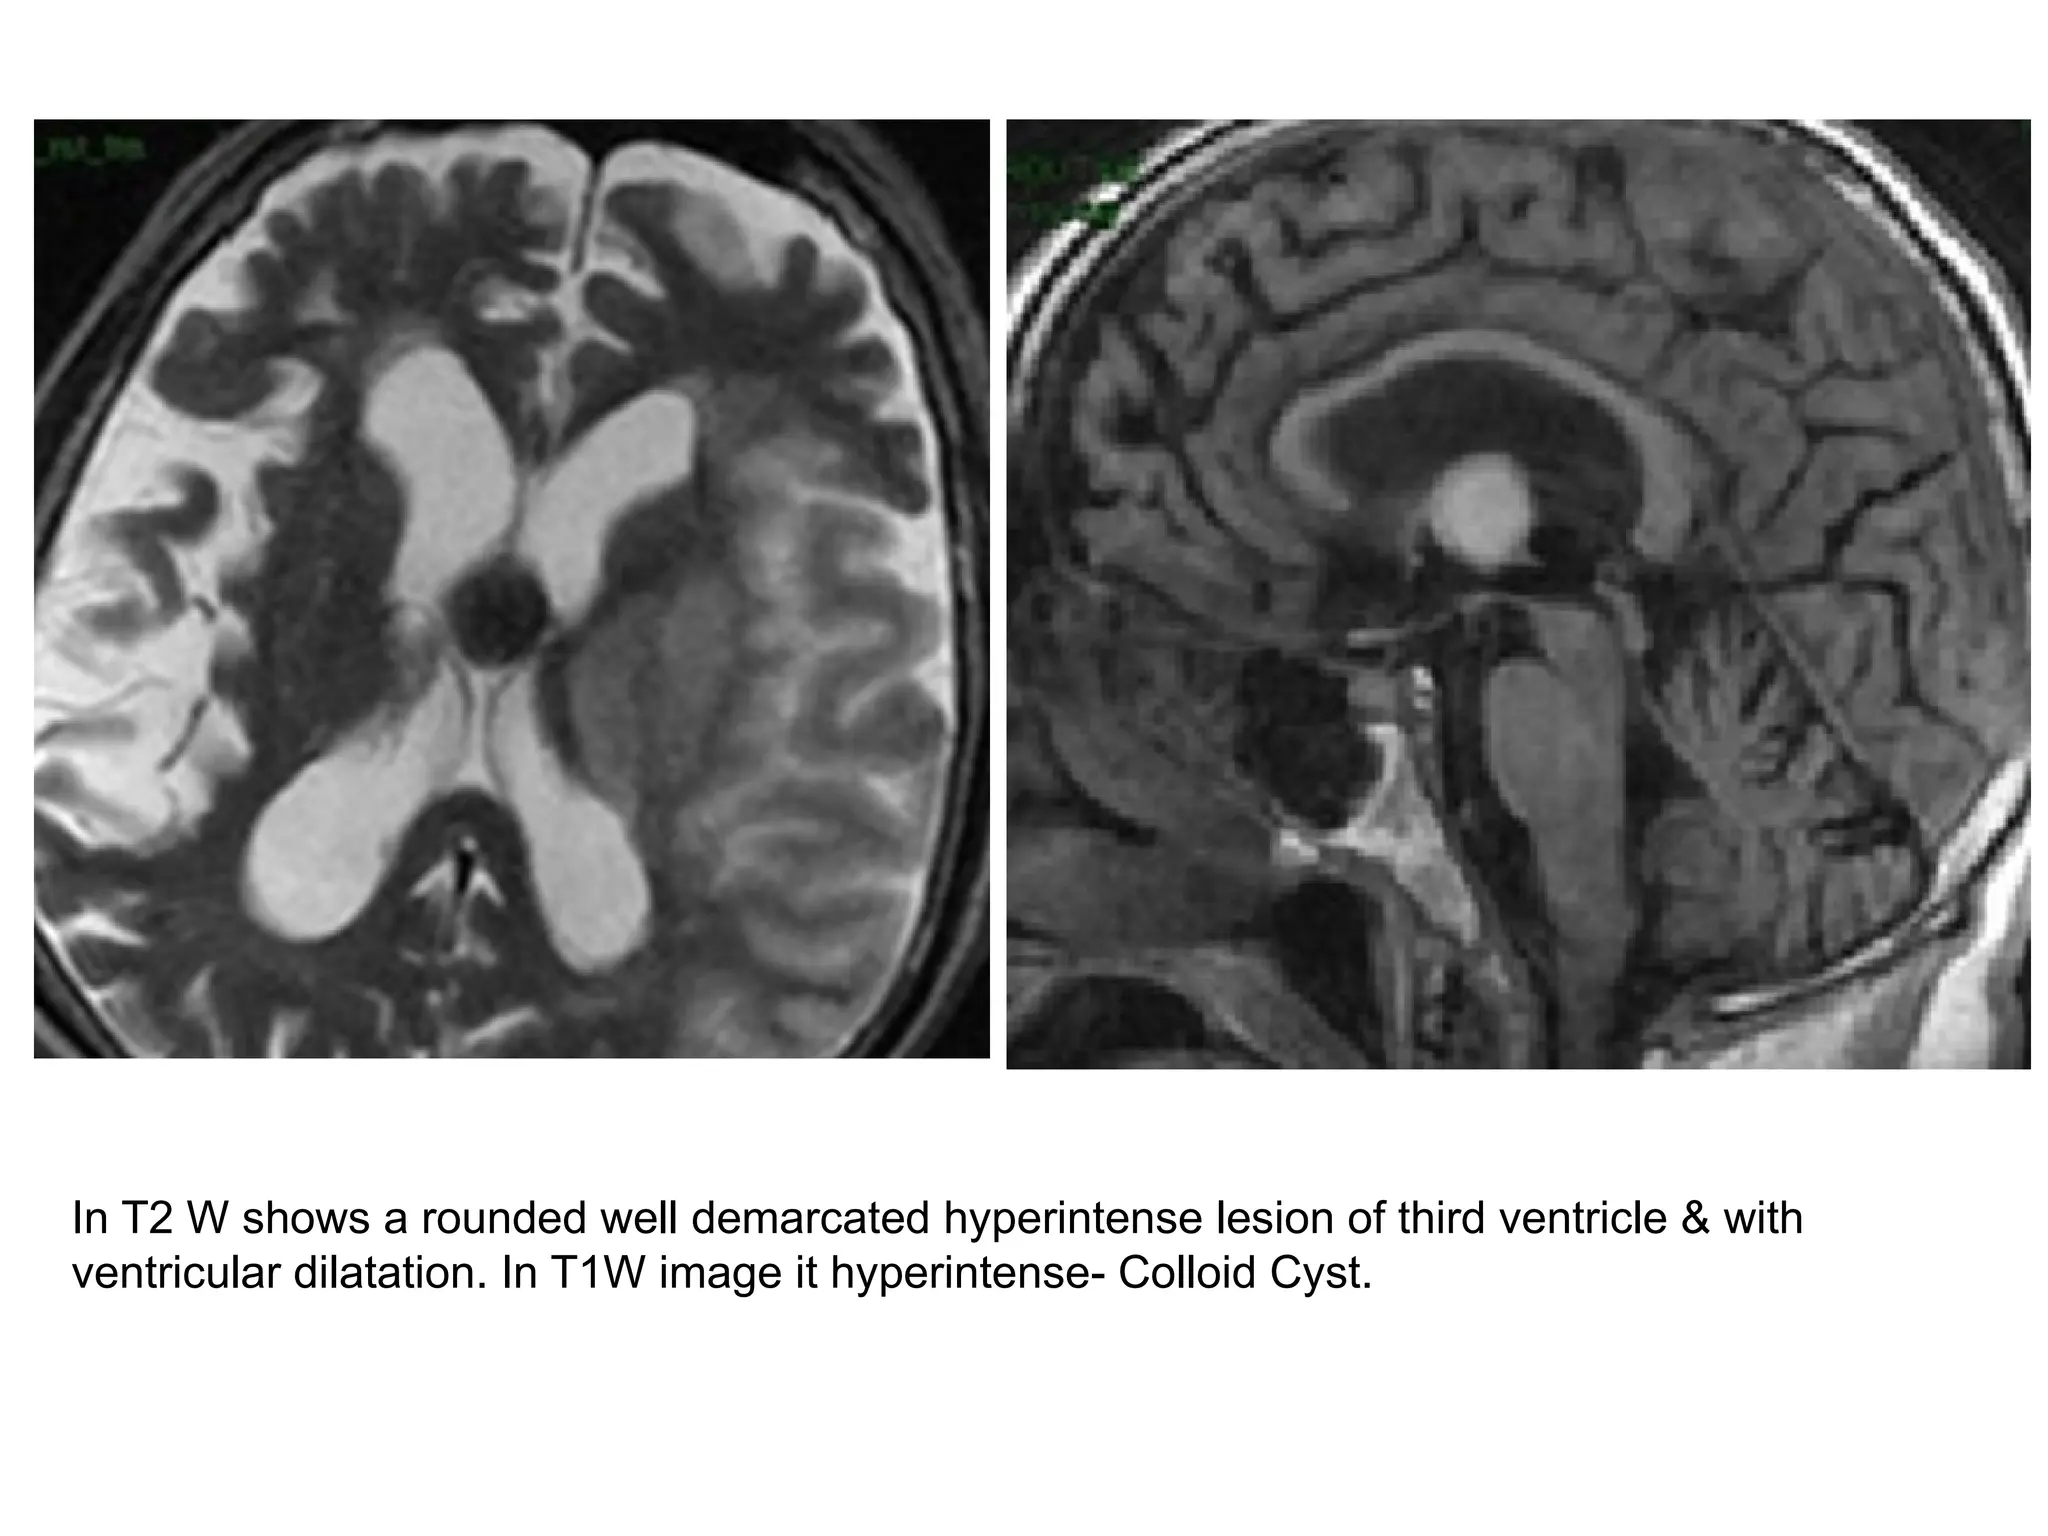

In T2 W shows a rounded well demarcated hyperintense lesion of third ventricle & with

ventricular dilatation. In T1W image it hyperintense- Colloid Cyst.

In T2 Wshows a rounded well demarcated hyperintense lesion of third ventricle & with ventricular dilatation. In T1W image it hyperintense- Colloid Cyst.